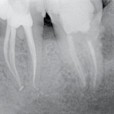

Preoperative x-ray: Upon diagnosis of pulp necrosis an initial endodontic treatment is indicated. The mesial root canals present a mineralized root canal lumen and a strong curvature and the distal canal an extremely curved apical third.

Postoperative x-rays: The endodontic treatment is performed after scouting of the root canal with a diameter 10 hand file and securing of the mesial root canals using the NiTi file One G. Shaping was carried out with TS1 and TS2 to the working length, the MB2 canal was prepared using…